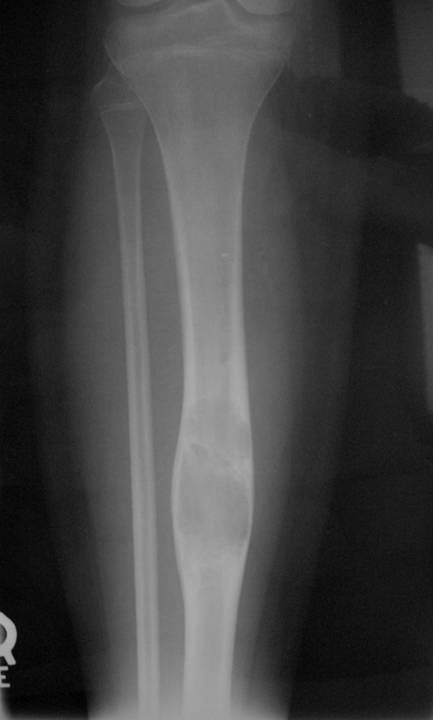

Sites:

- Predilection for tibia (90%)

- favoring diaphyseal portion of bone

Radiographic Presentation

- Sharply defined osteolytic defect (lobulated, multicystic, or “soap bubble”)

- May be considerable perilesional sclerosis